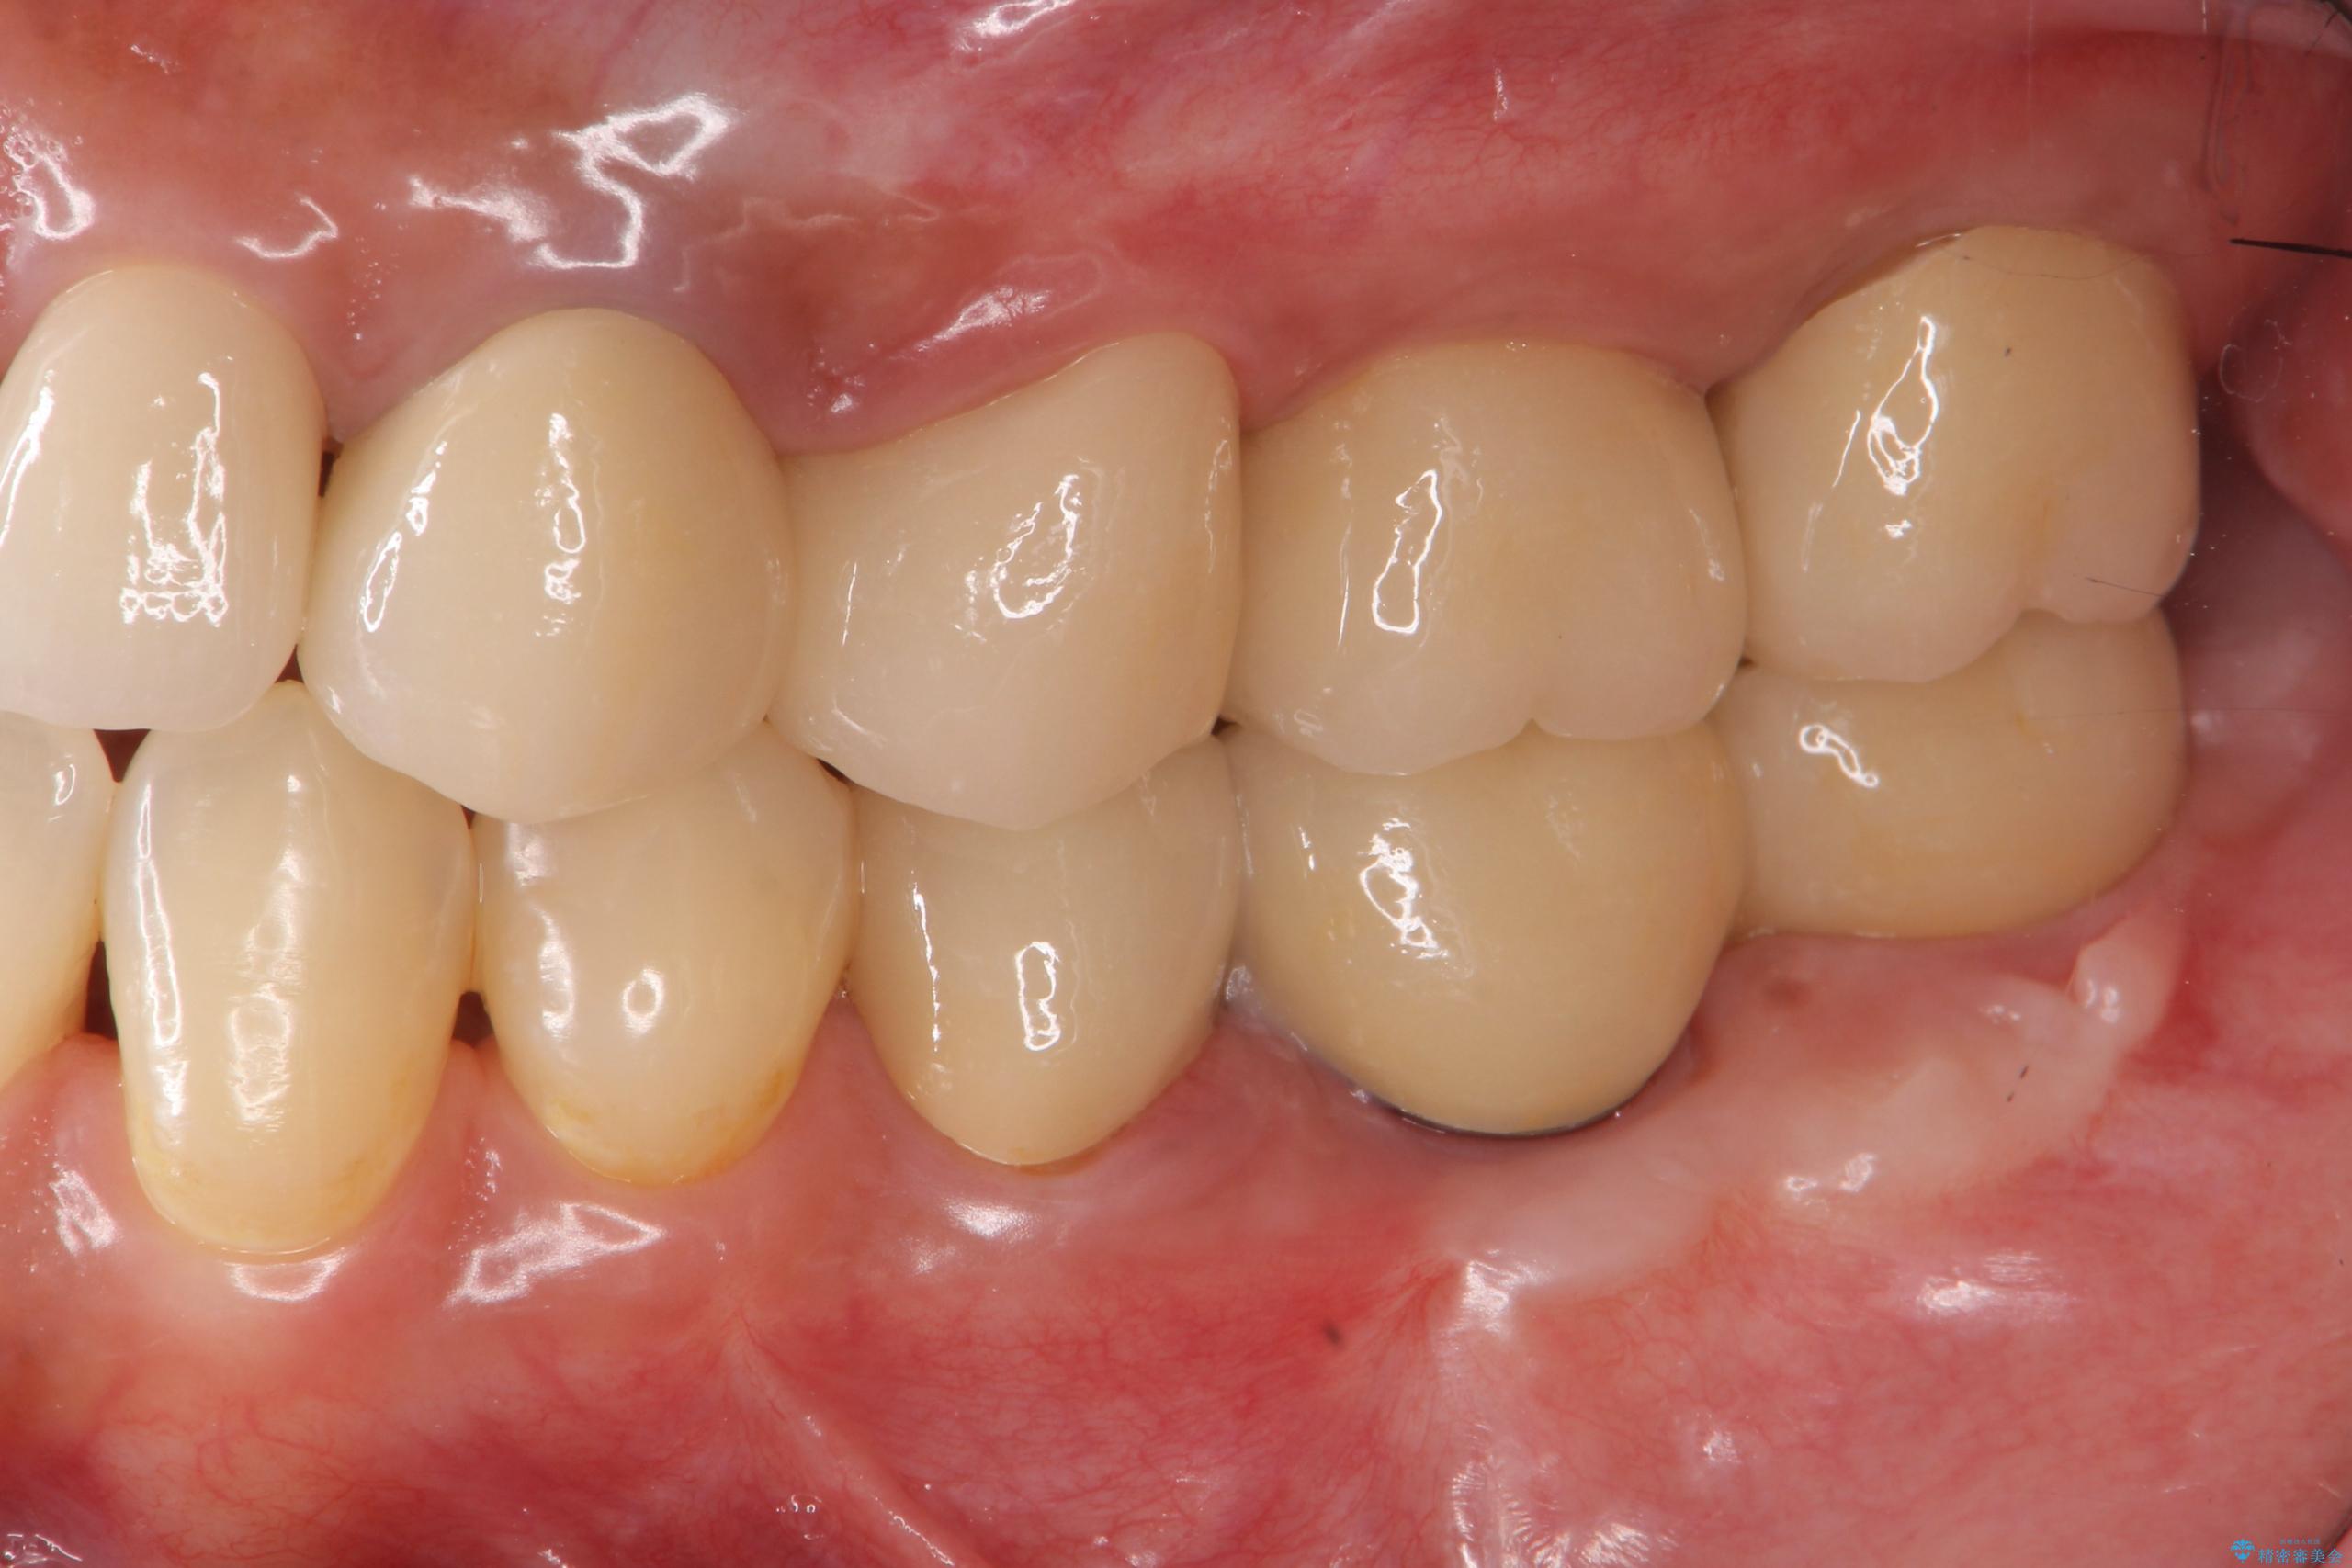

抜歯後、インプラントを用いて咬合機能を回復すると共に周囲に強固な角化歯肉を移植することによりより長期にわたり安定したインプラント周囲環境となるよう治療を計画します。

- 83.6万円(インプラント×2・アバットメント×2・クラウン×2)費用は治療当時の料金となります

インプラント周囲の角化歯肉が存在することにより、歯ブラシがしやすくなりインプラントにトラブルが起きる確率を減らしより長期的な予後を望むことができます。